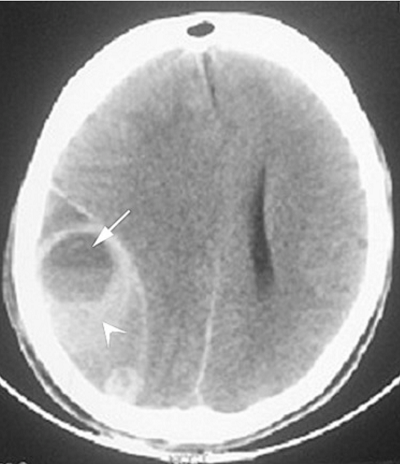

A 30-year-old male presents to the emergency department with severe headache and altered level of consciousness.